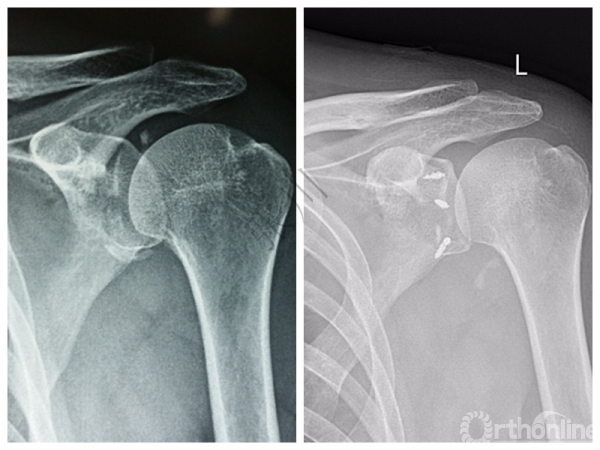

经典病例分享∣骨性Bankart损伤创伤性肩关节不稳定合并肩袖撕裂的治疗

1.影像学评估